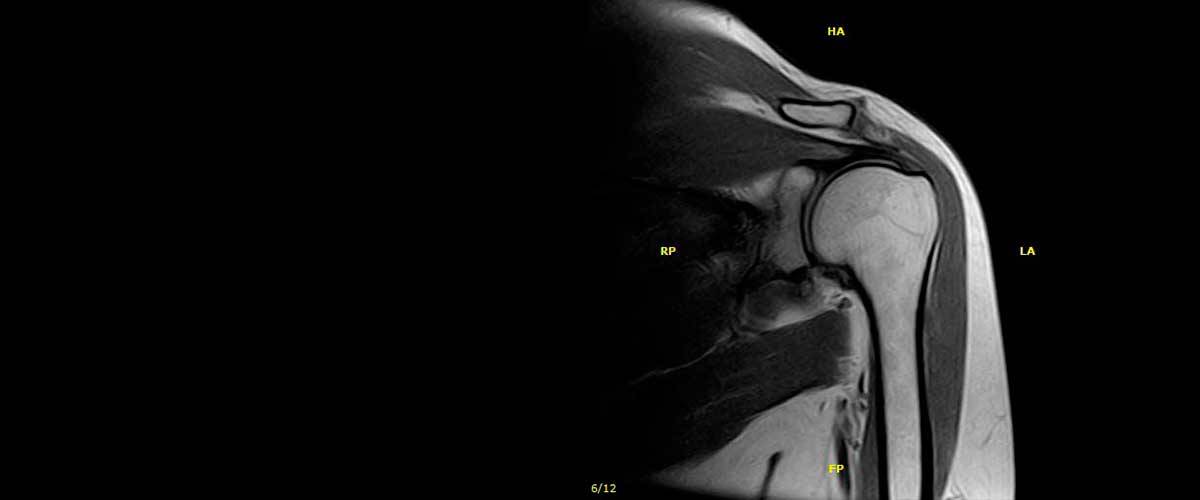

Contamos con equipos de resonancia magnética musculo-esquelética capaces de realizar exámenes con descarga de peso o bipedestación.

En nuestros centros se realizan estudios y diagnósticos de resonancia magnética musculo-esquelética

de Resonancia ,Magnética Musculo-Esquelética, de la marca italiana Esaote, es único en su diseño ya que nos permite realizar exámenes en bipedestación (el paciente estará de pie, para que se tenga otra perspectiva del comportamiento del cuerpo durante el examen).